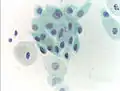

- Micrograph of a normal pap smear

- Normal squamous epithelial cells in premenopausal women

- Normal endocervical cells should be present into the slide, as a proof of a good quality sampling